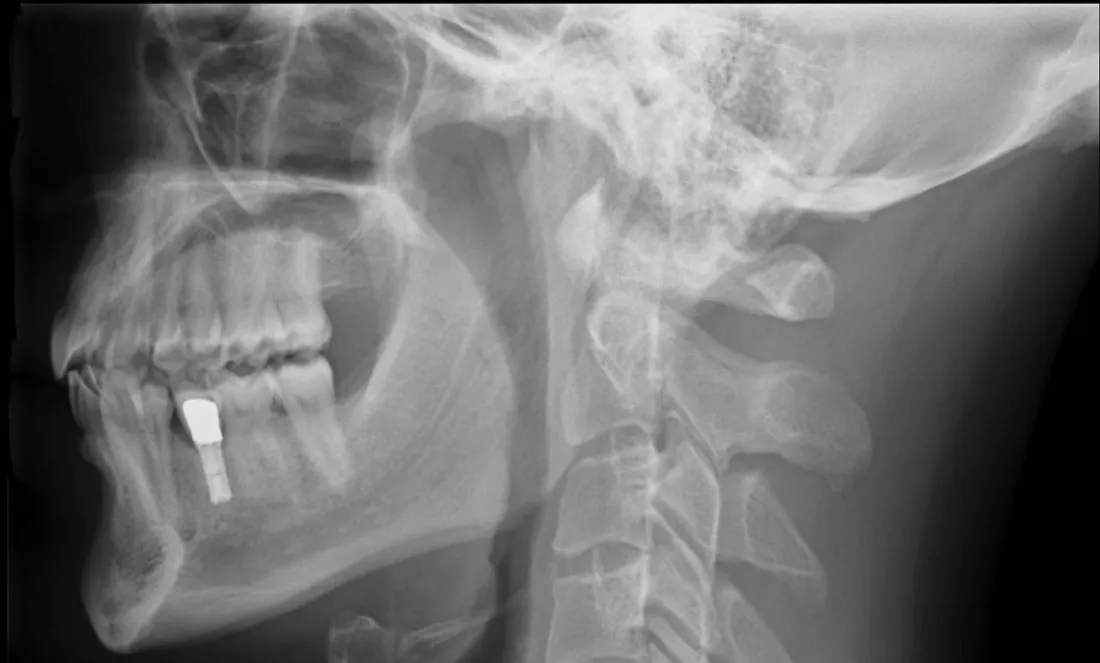

Bonne action : apportez vos vieilles radiographies chez votre pharmacien

A Châlons-en-Champagne, Epernay, Montmirail ou encore Sézanne, vous pouvez rapporter vos vieilles radiographies chez votre pharmacien.

Les radios sont particulièrement polluantes (jusque 300 ans pour la dégradation du sel d'argent dans les nappes phréatiques), mais si elles sont traitées, elles peuvent encore servir à de bonnes actions.